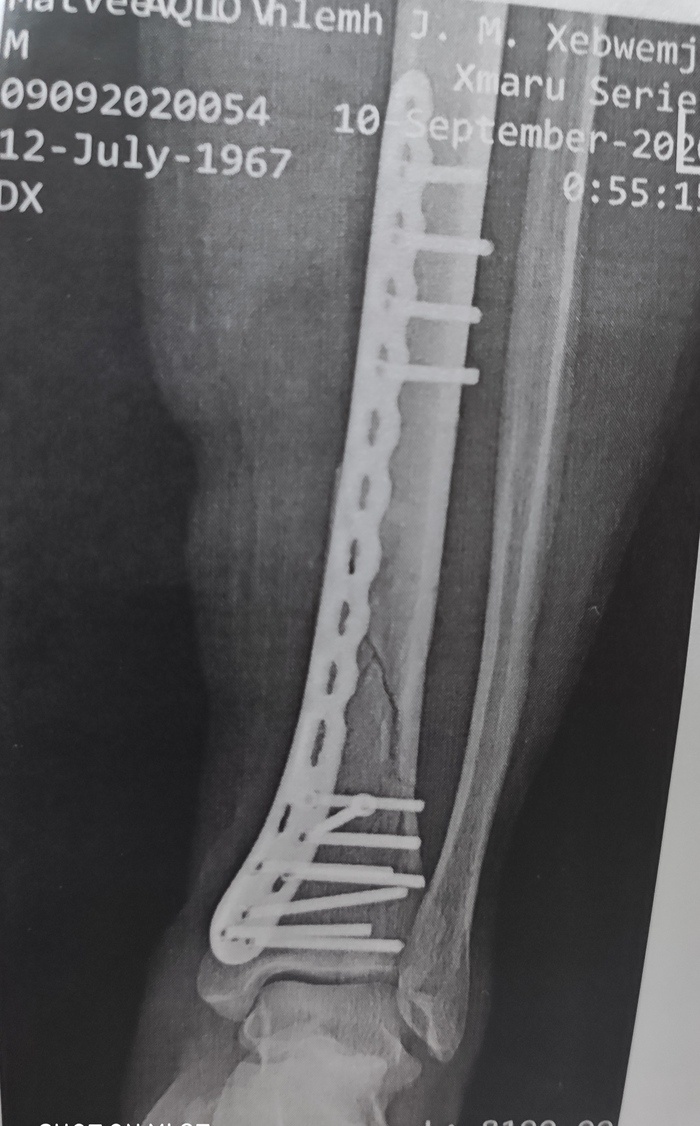

А мне лет 5 назад оперировали ногу (вставляли пластину). Вкололи спинальную анастезию и уложили на операционный стол. Закрыли нижнюю сторону простынкой и тут хирург (довольно молодой мужчина) включил музыку, при чем, не просто, а такой сборник всех песен из кинофильма Брат-2. И вот такое музыкальное сопровождение по своему воздействию мне очень хорошо теперь запомнилось. Значит, сверлят мне кость голени шуруповертом, каждый оборот сверла, ритмичными толчками четко чувствуется всем телом. Потом вкручивают шурупы и все это под саксофонные проигрыши, и слова " вечно молодооооой, вечно пьяяяный". (ну и другие некоторые песни от ныне иноагентов)) В общем, на короткое время, эмоционально я почувствовал себя эдаким робокопом, которого положили на ремонт. Надо отметить, что операцию хирург провел хорошо и удачно. Спасибо ему за это. Пост автора grabador. Подписаться на Пикабу Познавательный. и Пикабу: Истории из жизни.

А мне лет 5 назад оперировали ногу (вставляли пластину).